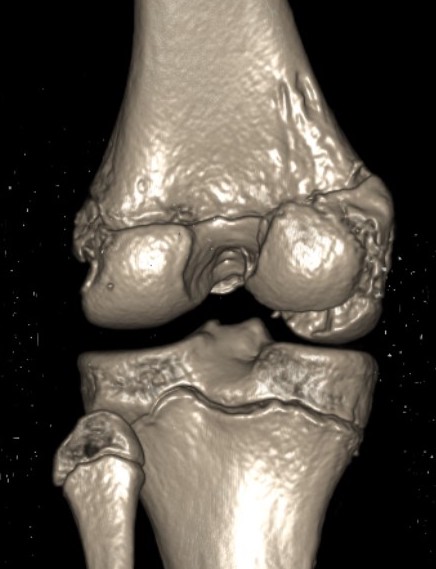

CT

Aids surgical planning

Medial Hoffa CT 1Medial Hoffa CT 2Medial Hoffa CT 3Medial Hoffa CT 4